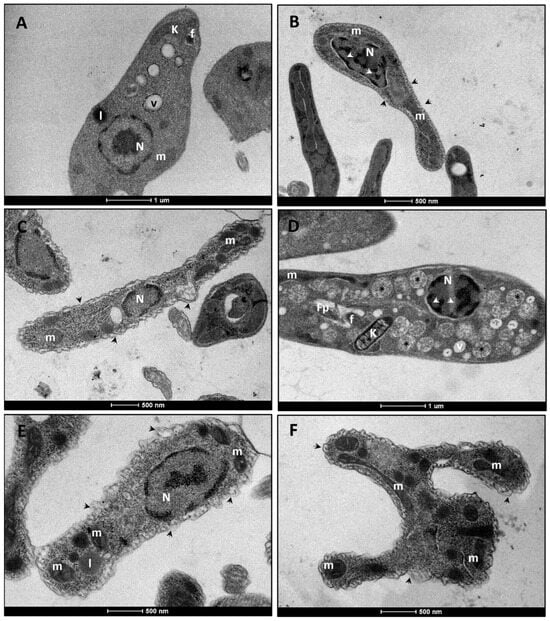

3.2.1. L. infantum Promastigote Forms

3.2.2. L. infantum Amastigote Forms